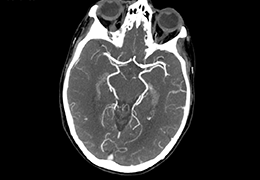

成像智能。

Eclipse 成像智能功能提供强大的处理能力和最佳质量的影像,同时减少质量错误并提高剂量效率。

凭借 AI、专有算法和先进的影像处理能力,提供出色的影像质量和无与伦比的诊断信心。

与标准影像处理相比,智能降噪功能可使客户降低辐射剂量,而不会损失影像质量。这在新生儿和儿科成像中尤其重要,在这种情况下以尽可能低的剂量成像至关重要。